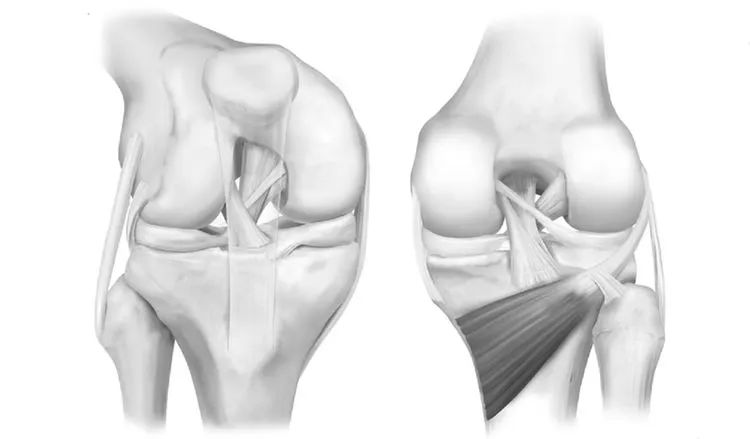

7、半月板后角内侧半月板周径较大,形似“C”形,后角宽,前角窄,后角宽度几乎是前角的2倍;外侧半月板周径小而面积大,形似“O”形,中部宽阔,前后角匀称,而且内外侧半月板后角为了适应内外侧胫骨髁和股骨髁而有着不完全相同的形态。